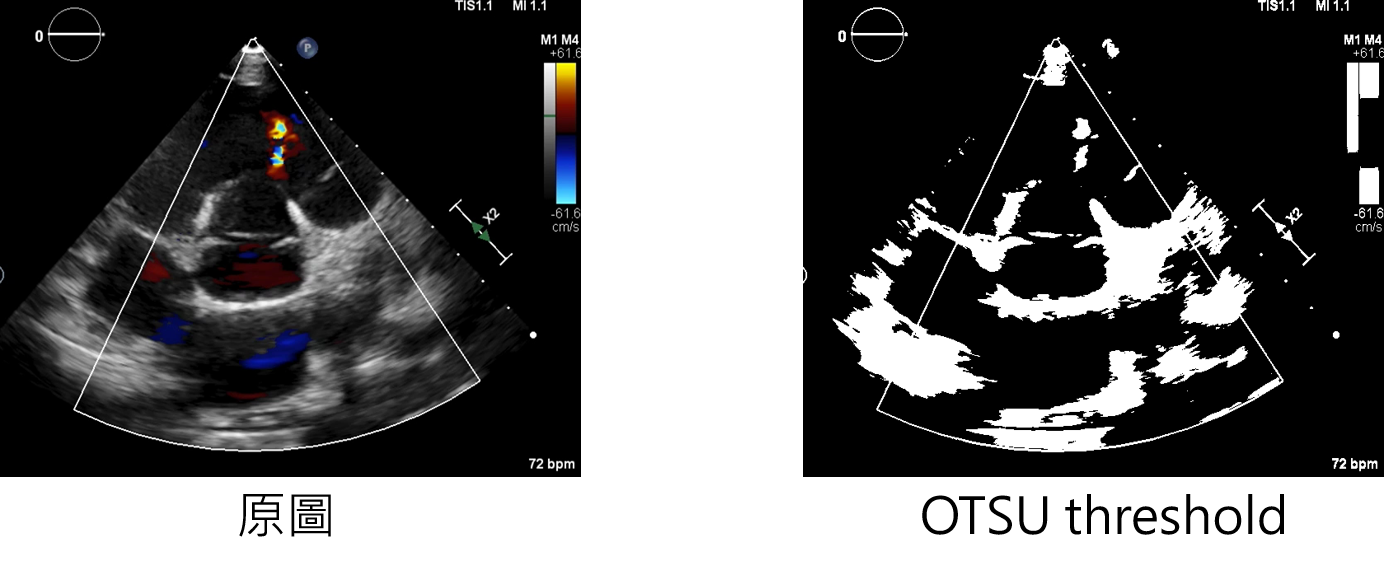

參數說明

OTSU:增強方法

輸入範例:

datagen=CustomDataGenerator(fun="OTSU",dtype=int)